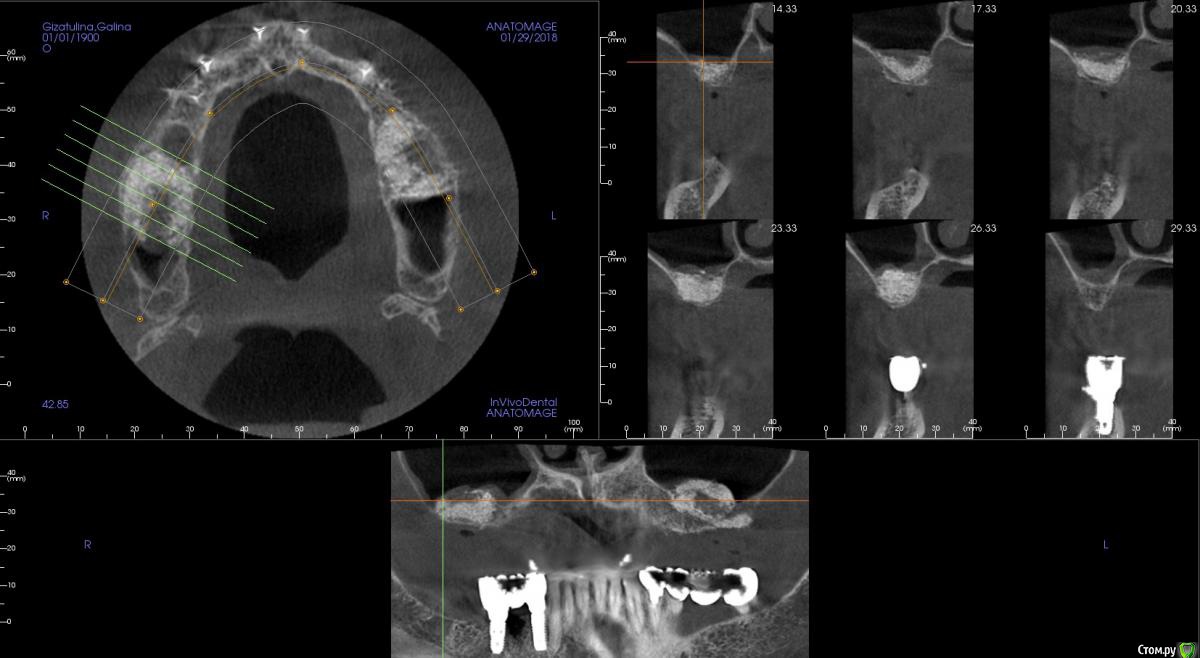

kamranchick Опубликовано 30 января, 2018 Поделиться Опубликовано 30 января, 2018 Господа приветствую, а можно ли как то оценить операцию синуса до сверления?Хорошо был произведен или нет? сделал с 2 сторон , но во 2 сегменте какая то странная ситуация.повторное кт через 6 месяцев. Ссылка на комментарий

red_butler Опубликовано 31 января, 2018 Поделиться Опубликовано 31 января, 2018 С обеих сторон странно выглядит Ссылка на комментарий

Evikrol Опубликовано 31 января, 2018 Автор Поделиться Опубликовано 31 января, 2018 Маловато. Сколько графта на пазуху? Ссылка на комментарий

kamranchick Опубликовано 1 февраля, 2018 Поделиться Опубликовано 1 февраля, 2018 получилось по грамму на каждую сторону+ губки гемостатические Ссылка на комментарий

Борис80 Опубликовано 2 февраля, 2018 Поделиться Опубликовано 2 февраля, 2018 слева , видимо, десна вросла в окно, я бы предположил...На вскидку скажу, что на каждую пазуху минимум 2 грамма планирую, тем более когда там только кортикалка, Вы плотно "пакуете" материал ? Я бы сверлился и смотрел плотность Ссылка на комментарий

kamranchick Опубликовано 2 февраля, 2018 Поделиться Опубликовано 2 февраля, 2018 слева , видимо, десна вросла в окно, я бы предположил...На вскидку скажу, что на каждую пазуху минимум 2 грамма планирую, тем более когда там только кортикалка, Вы плотно "пакуете" материал ? Я бы сверлился и смотрел плотность торк 40 на каждой стороне, все хорошо получилось, но в 2 сегменте какая то кость непонятная вот как определять без сверления че и как, нигде и не описано Ссылка на комментарий

Борис80 Опубликовано 3 февраля, 2018 Поделиться Опубликовано 3 февраля, 2018 на кт имплантов нет, но они установлены? торк 40 где получился? Если уже установлены импланты, то теперь ждите ойтеста) Ссылка на комментарий

kamranchick Опубликовано 3 февраля, 2018 Поделиться Опубликовано 3 февраля, 2018 на кт имплантов нет, но они установлены? торк 40 где получился? Если уже установлены импланты, то теперь ждите ойтеста)отправил на 7 месяцев погулять)) торк 40 везде получился. скину через пару дней панорамку Ссылка на комментарий